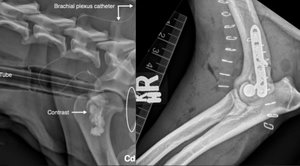

1/ Opioid-free anaesthesia (OFA) in a springer spaniel sustaining a lateral humeral condylar fracture undergoing surgical repairGeddes, AT., Stathopoulou, T., Viscasillas, J., Lafuente, P.Veterinary Record Case Reports, 2019, 7: e000681.Résumé : A two-year, three-month-old male entire springer spaniel presented for right thoracic limb lameness. Radiographs of both elbows revealed a right lateral humeral condylar fracture. Local anaesthesia using bupivacaine was supplied to the site using a continuous stay peri-neural catheter at the brachial plexus. The fracture was stabilised using a lag screw and locking compression plate (LCP) plate. No response to surgical stimulation was noted on the patient’s vital parameters during anaesthesia, systemic analgesia was deemed not to be required. Bupivacaine was administered through the brachial plexus catheter every seven hours postoperatively. Pain scores were noted to be low, hence no systemic opioids were provided. The use of a continuous peripheral nerve block allowed for cold packs and passive range of motion exercises the same day of surgery. It also allowed for a lack of requirement of systemic opioids for the duration of hospitalisation.